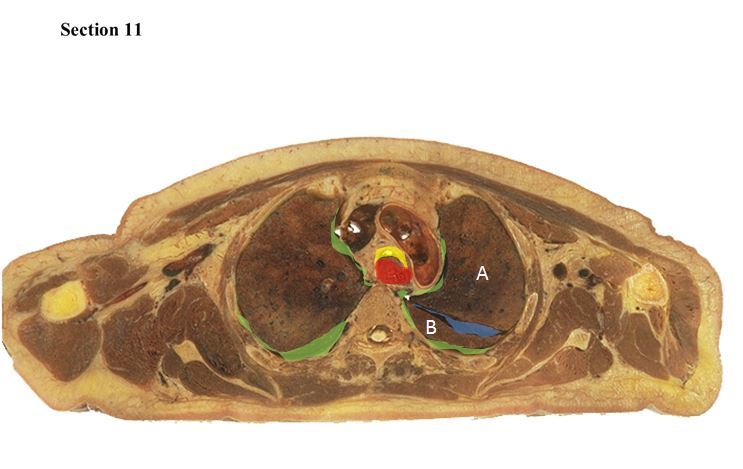

11

Q

The blue space is the _____ and it separates structure A which is the _____ of the lung from structure B which is the _____ of the lung.

A

oblique fissure

superior lobe

inferior lobe